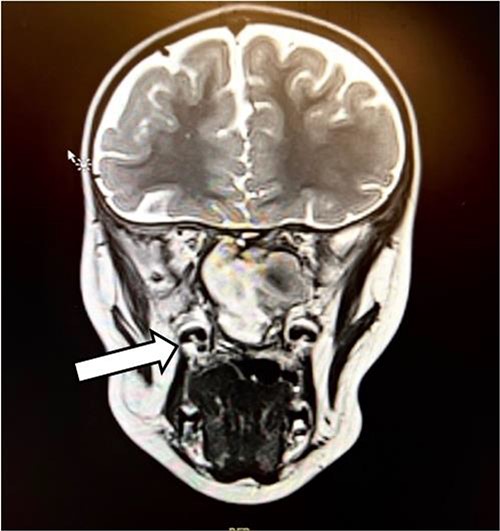

The patient had undergone computed tomography of the paranasal sinuses (CT PNS) and magnetic resonance imaging (MRI) brain with contrast. The MRI showed a heterogeneous mass predominantly occupying the left nasal cavity, left maxillary, and sphenoid sinus, destructing the osseous structure, as well as extending to the medial aspect of the left orbital wall causing minimal proptosis (Figs 1 and 2). Magnetic resonance angiography showed no prominent feeding vessel of the mass. CT PNS demonstrated a heterogenous soft tissue nasal mass extending into the sphenoid wing through the sphenoid sinus, causing skull base erosion but no intracranial invasion.